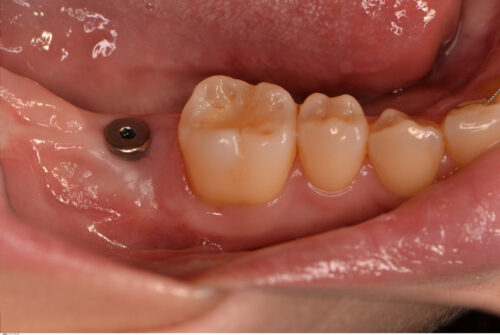

下顎7番にインプラントを埋入。

上部構造を装着しました。